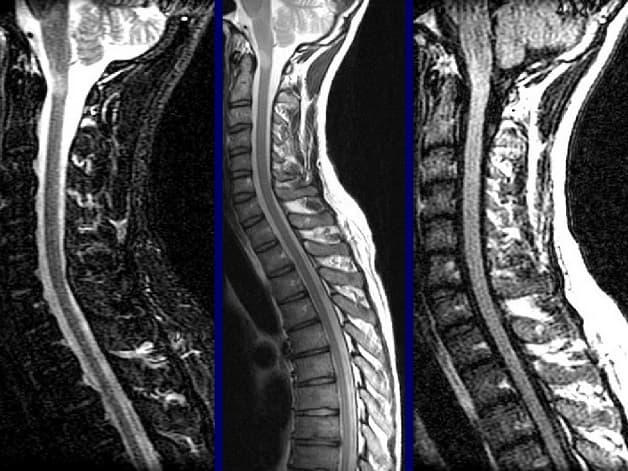

– MRI cột sống

Chụp cộng hưởng từ có khả năng khảo sát nhiều cơ quan trên cơ thể. Tùy vào từng vị trí chụp mà có các hạng mục chụp MRI tương ứng như sau: